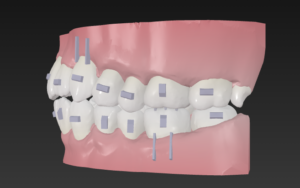

この歯並びが治る原理は

歯と歯の間を0.2から0.6ミリ削る

IPRという医療行為を行い

スキマをつくり

これを利用して歯をキレイに整列

🔶アフター🔶

右

左